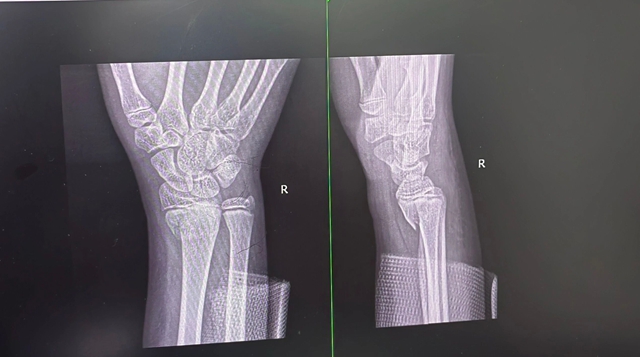

紧急完善影像检查后,诊断结果很快明确:中医诊断为“骨折病(气滞血瘀证)”,当“续筋接骨,活血化瘀”;西医诊断——右肱骨髁上骨折、右桡骨远端骨折,还合并正中神经损伤。

右肘关节肿胀得厉害,明显变了形,皮肤上还散着青紫瘀斑和水泡,一碰就疼,轻轻活动,疼痛更甚,甚至能感触到骨头摩擦的声音;右腕关节同样肿胀,活动疼痛,症状与肘关节如出一辙,腕部呈轻微下垂状态,想往上抬都没力气,手指麻木感和伴有食指屈曲活动障碍也始终没有缓解。